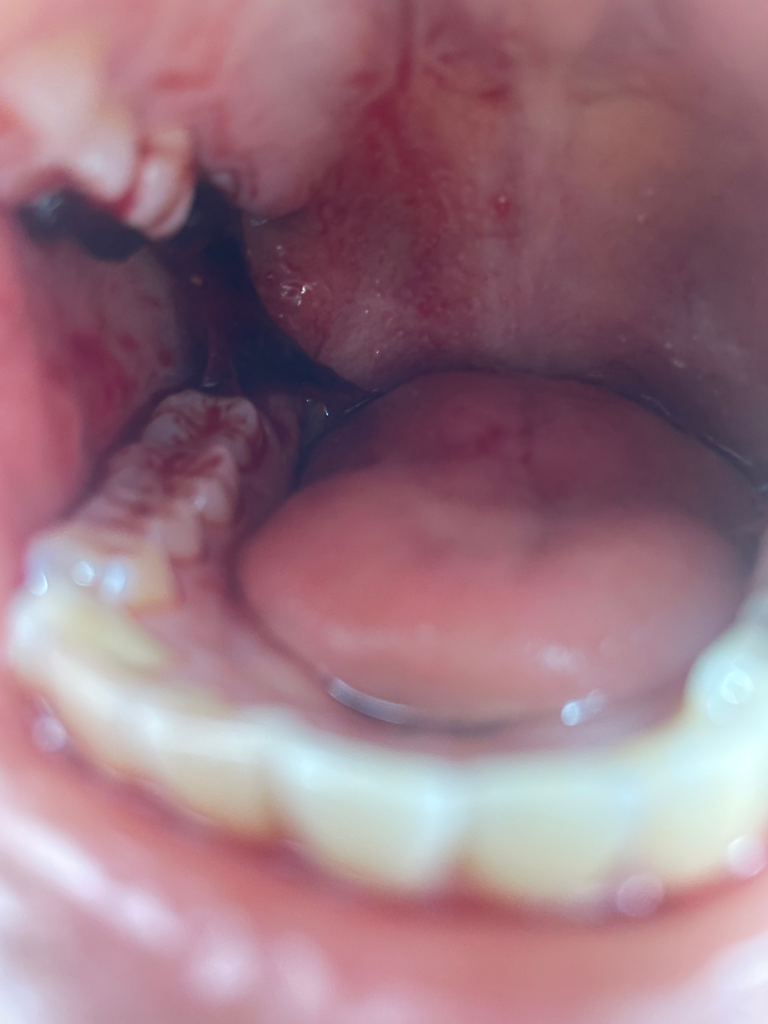

사랑니 피떡 이 상태인데 괜찮은가요?

오늘 오전에 사랑니 뽑았구

뽑은지 14시간 정도 됐습니다

피떡이 위아래가 이어져있고 지혈도 잘 안 됐는지 피가 계속 나는 것 같은데...

치과에 다시 가봐야 할까요?

• 1번 째 사진

• 안녕하세요. 김철진 치과의사입니다.

지혈이 안되시는거 같은데 치과에 가셔서 다시 후처치를 받으셔야될것같습니다. 피가 많이 나는거 같네요.

• 안녕하세요. 송우식 치과의사입니다.

사랑니 발치후에 1-2일정도는 피가 나올수 있기에 정상적인 반응이며, 멸균거즈를 물고 지혈을 지키길 권합니다. 묻어나오는 피는 벧지말고 삼키길 권합니다.